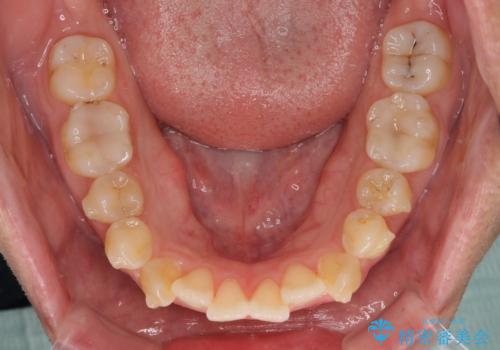

開咬とデコボコを整える インビザライン矯正治療

- 前歯の開咬と叢生を気にして来院された患者様です。

開咬の治療は、前歯を閉じるように動かすとともに、上下臼歯を圧下(骨内にめり込ませる)させることで進めて行きます。

インビザラインは臼歯の圧下を効果的に行えるため、インビザラインを用いて矯正治療を行うこととしました。また、アンカースクリューを用いて、口元の突出感の改善を図りました。